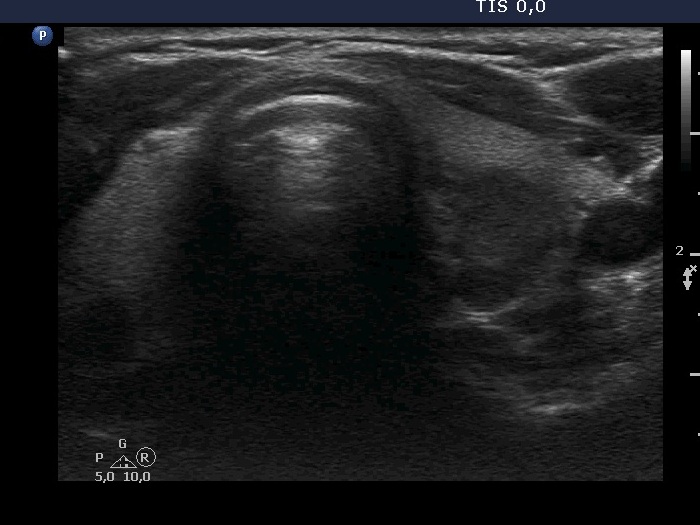

The borders of the nodule - case 2115 |

Clinical presentation: A 42-yr-old woman was referred for evaluation of a nodular goiter detected by chance on carotid Doppler examination.

Ultrasonography. The thyroid was echonormal. There was a mass in the dorsal part of the left lobe. The lesion presented parts with different echogenicities.

Comment. The issue is whether the lesion is composed of one or more nodules. In the former case it has lobulated margins, in the latter this is a non-pathological lobulation. Nonetheless, the question is only theoretical because the nodule requires cytological evaluation.